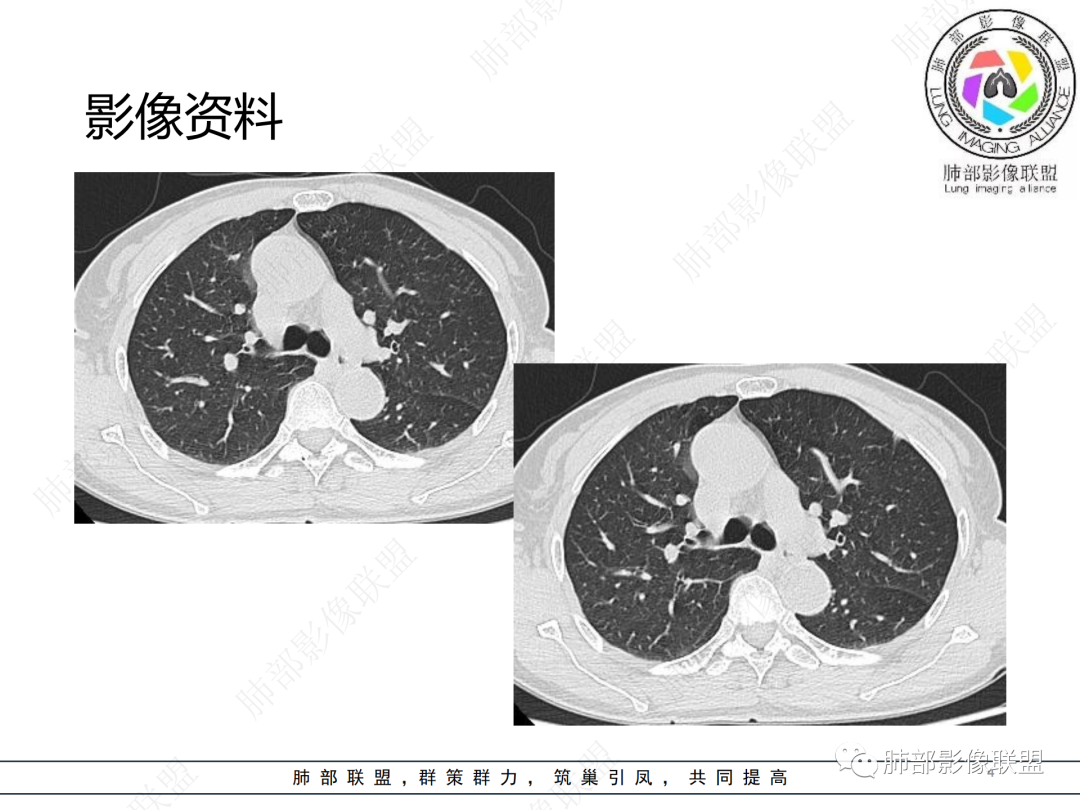

中年女性,咳嗽,胸部CT左肺上叶长条状实变影,周围磨玻璃影,边界清楚,病灶近端似乎有点状高密度影,首先考虑炎性肉芽肿,其次腺癌待排

晨读病例,中年女性,咳嗽一年,左肺上叶胸膜下三角形阴影,局部收缩,周围边缘清晰的磨玻璃影,考虑炎性病变,OP。鉴别腺癌。

左肺上叶胸膜下混合磨玻璃结节,边界似清非清,其内可见增粗血管,抗炎效果差,1年复查增大,考虑粘液腺癌,鉴别慢性炎症

左肺上叶实变影伴磨玻璃影,边界清楚,考虑腺癌,

晨读:慢性病程,胸膜下,边界似清不清,粘液腺癌。

左肺上叶磨玻璃密度,血管增粗,边界清,考虑腺,鉴别炎性

晨读,左肺上叶胸膜下混合磨玻璃密度影,内部可见血管增粗,抗炎治疗效果不佳,一年复查增大,考虑腺癌可能

晨读 左肺上叶胸膜下条片状混杂密度影,膨胀及收缩不明显,周围磨玻璃影边缘似清非清。胸膜糊墙,复查较一年前病灶增大,首先考虑粘液腺癌。

左肺上叶混合磨玻璃病灶,磨玻璃边界似清非清,病灶可见增粗血管,边缘似有月牙征,关键病史与2021年比较有增大,考虑恶性可能大,粘液腺癌、腺癌可能。鉴别慢性炎症。

老年女性,慢性咳嗽,治疗复查无效,咳少量白色粘痰,左肺上叶前段胸膜下亚实性结节,形态呈树上“蘑菇”征,并见“小圆圈”影,周边模糊的磨砂玻璃影,首选粘液腺癌,病灶定位下经皮肺穿刺活检!

晨读:患者,女,65,咳嗽1年,加重1月。胸部CT:左肺上叶胸膜下不规则mGGN,实性灶有膨隆,收缩不明显,周围磨玻璃影似清非清,内可见空泡/细支气管断面?胸膜糊墙。复查较一年前病灶增大。考虑粘液腺癌?鉴别TB、NTM。

晨读左肺上叶胸膜下结节,混合密度磨玻璃,边界似清非清,支气管腔内粘液,警惕粘液腺癌

左肺病灶,周围似清非清,考虑腺癌可能性大,鉴别炎性肉芽肿

左肺上叶混合磨玻璃结节影,部分边缘小叶间隔阻挡,周围磨玻璃影似清非清,内可见空泡,复查较一年前病灶增大。考虑粘液腺癌?鉴别炎性肉芽肿

左肺上叶前段混合磨玻璃结节,实性部分局限性凹陷,磨玻璃影边缘似清非清,老年女性,1年多胸痛病史,考虑腺癌,粘液性腺癌

肺部联盟晨读:老年女性,病程1年,混合磨玻璃密度,周围边缘较清楚,腺癌>炎症

晨读老年女性,左肺上叶胸膜下条状实变影,周围可见絮状磨玻璃影,边界较清,可见小叶间隔阻挡月牙征,抗炎无效,复查增大,考虑腺癌。

左肺上叶结节影,周围边界清楚磨玻璃影,考虑粘液腺癌

左肺上叶胸膜下混合磨玻璃结节,边界不甚清楚,抗炎无效,目前增大,考虑粘液腺癌

左肺上叶混合密度的结节,部分磨玻璃边界偏清晰,内部血管似有增粗,病灶较一年前增大,肿瘤要警惕。

左上叶混杂密度结节,边界似清非清,其内血管影增粗扭曲,年度复查增大,白色粘液痰,有树上蘑菇征?综合分析考虑结节型粘液腺癌

混合磨玻璃结节,密度不均,短毛刺,周围磨玻璃边界较清,复查病灶增大,考虑腺癌,鉴别炎性肉芽肿。

左肺上叶混合结节伴磨玻璃影,边界清楚,考虑腺癌

这个要做个重建就好了  可以整体观察这个病灶 1.边界清  2复查有增大,考虑恶性是有可能的

晨读,混合磨玻璃结节,内见增粗血管影,病史长,结节型粘液腺癌,抗炎后短期复查。